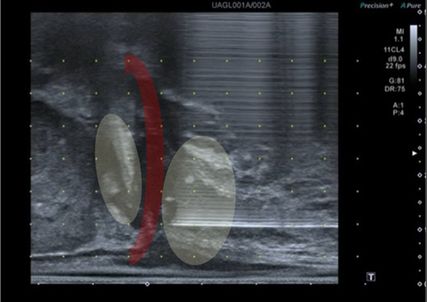

Abb. 2: Sonografische Darstellung der tiefen Beckenbodenmuskulatur (rot) und der Prostataapex. In Gelb dargestellt sind die Applikationsorte der tiefen Lokalanästhesie vor perinealer Prostatabiopsie

Für eine schmerzarme Biopsie ist eine Lokalanästhesie notwendig. In der Regel werden 5–7ml Lokalanästhetikum (z.B. Mepivacain 1%) bei 11 und 1 Uhr oberhalb des Anus subkutan injiziert. Zusätzlich sollte eine tiefergehende Anästhesie der Beckenbodenmuskulatur erfolgen (Musculus transversus perinei superficialis, Musculus levator ani), mit weiteren 5–10ml Lokalanästhetikum je Seite (Abb. 2).